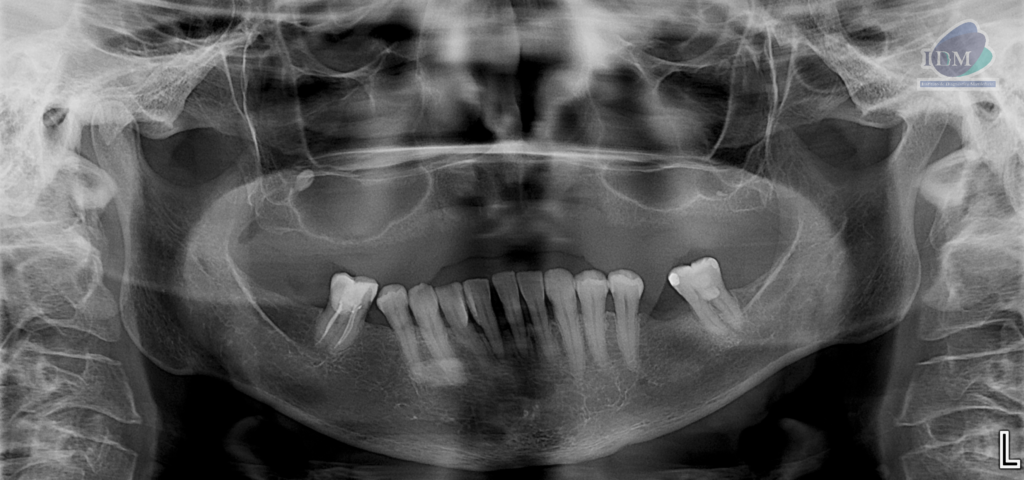

En las reconstrucciones 3D se representa de manera didáctica la localización y relación del sialolito con estructuras adyacentes. (Figura 4).

RECONSTRUCCIÓN 3D

- Características imagenológicas compatible con Sialolito en conducto de Wharton de la glándula submandibular del lado derecho.